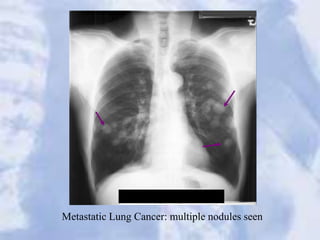

Metastatic Lung Cancer: multiple nodules seen

Metastatic Lung Cancer:multiple nodules seen